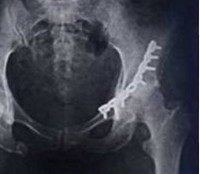

S32.4 Перелом вертлужной впадины